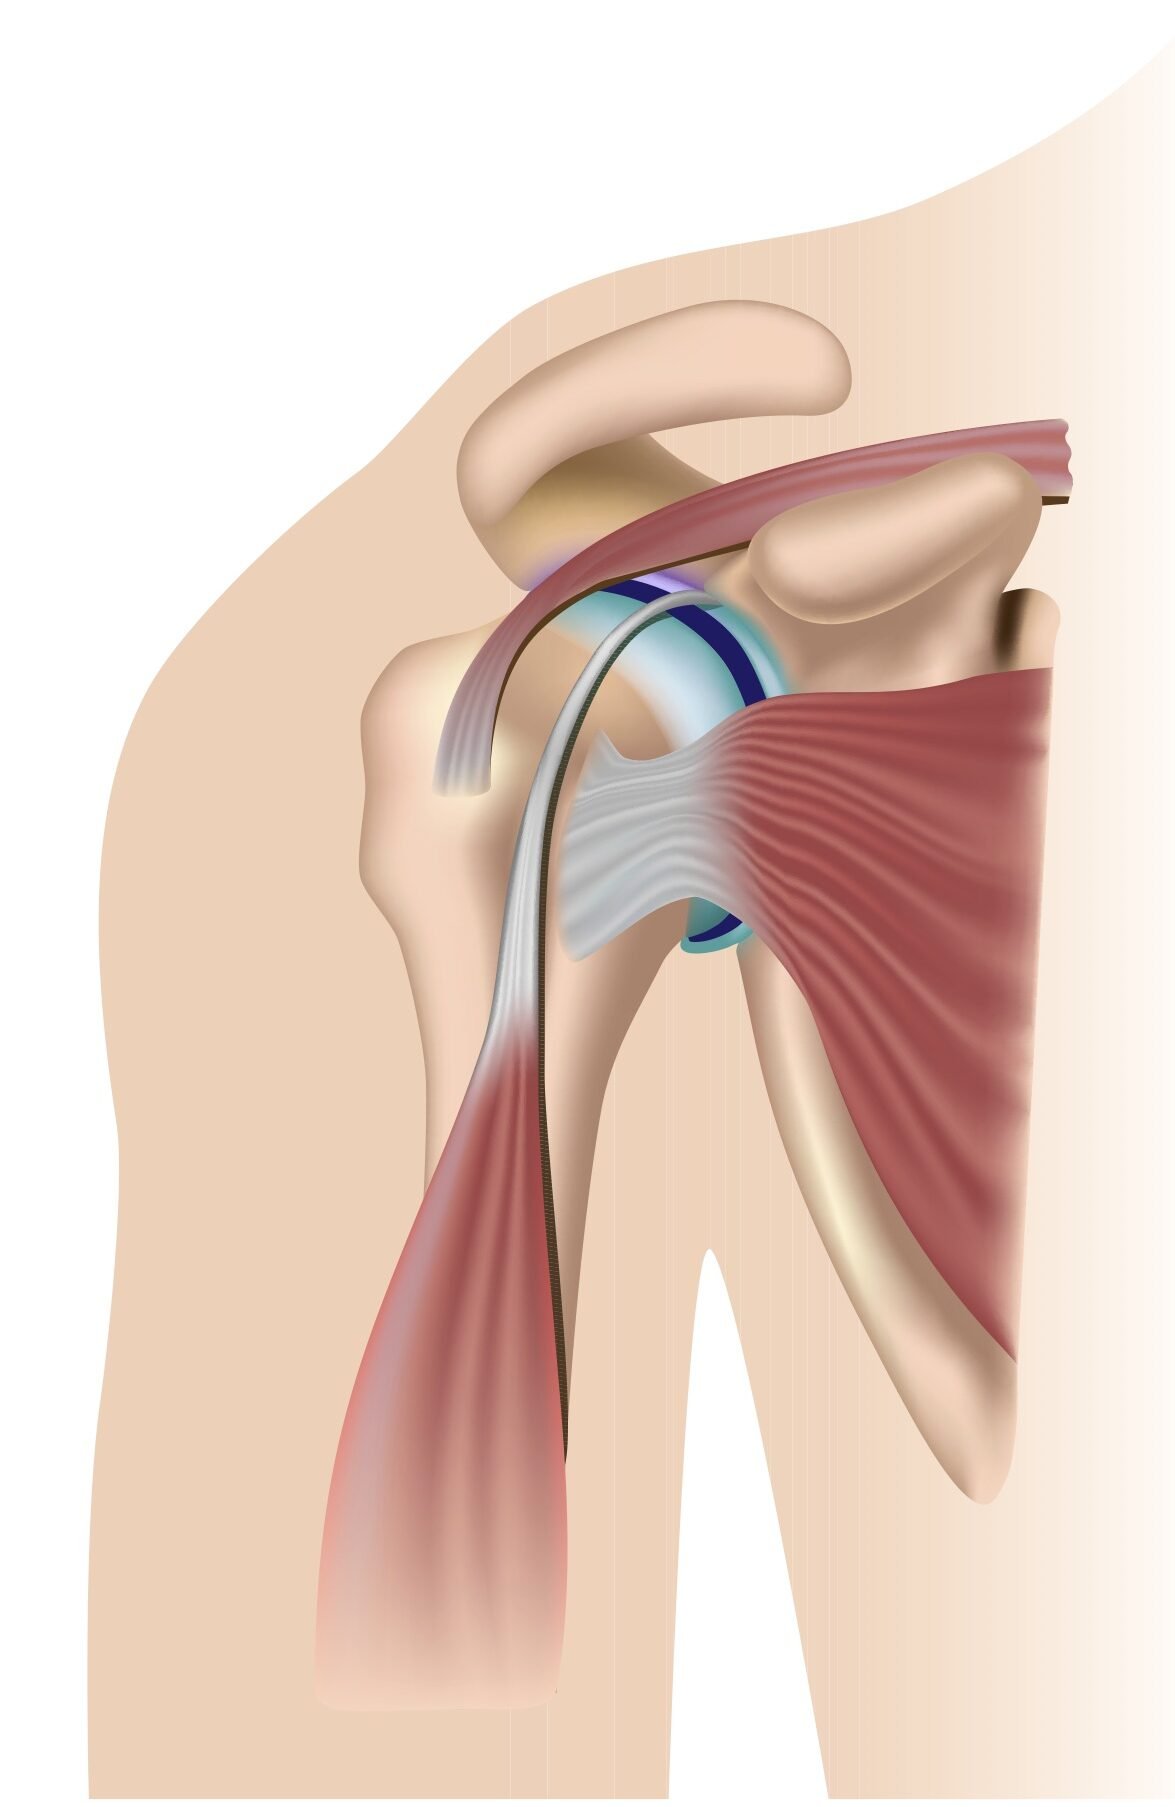

Фотографии мышц ротаторной манжеты плеча